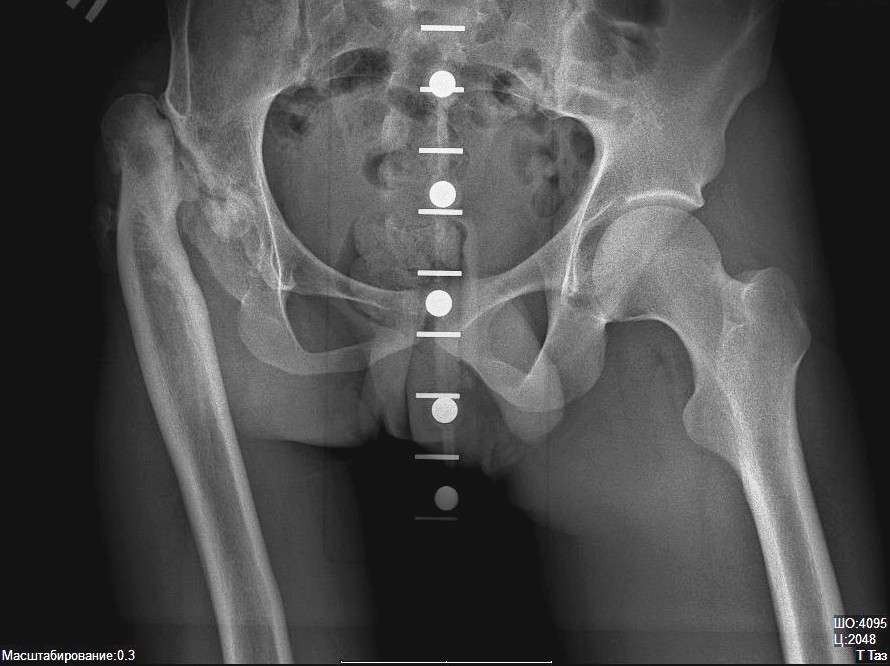

- Тазобедренный.

Основа распознавания анкилоза – визуализирующие методики, такие как рентгенография костей и суставов, компьютерная или магнитно-резонансная томография. С их помощью определяется сужение и прерывистость суставной щели или ее полное заращение.